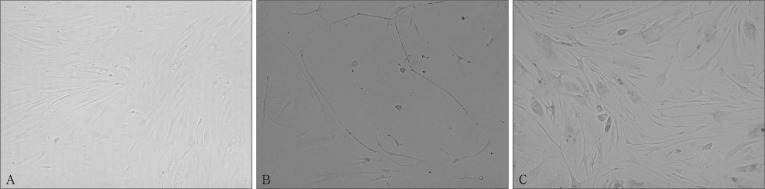

2.3. 转染后细胞形态及表型

倒置相差显微镜下观察,转染hTERT后的PDLCs与正常PDLCs形态相似,为长梭形,呈典型的纤维细胞特征。未转染细胞和转染空载体后的细胞传15~16代后生长缓慢,逐渐死亡,而转染hTERT后的PDLCs生长迅速,增殖稳定(图3)。

图 3. 转染前后细胞形态 倒置相差显微镜 × 100.

Fig 3 Morphological characteristics of cells before and after transfection inverted phase contrast microscope × 100

A:正常PDLCs;B:传代至第16代PDLCs;C:转染hTERT后第35代PDLCs。